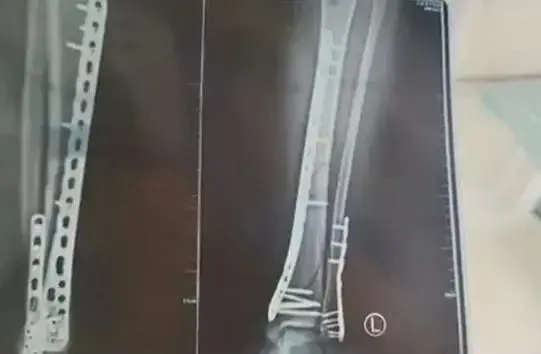

6月1日,甘肃兰州的武女士在下楼时不慎摔倒,导致左腿粉碎性骨折。当时她穿着厚度为7厘米的洞洞鞋。

武女士表示,由于鞋底较厚且中间有凹陷,她在下楼梯时踩到了凹陷处,脚没有踩实,导致身体前倾,重心全部集中到腿上,*终导致骨折。